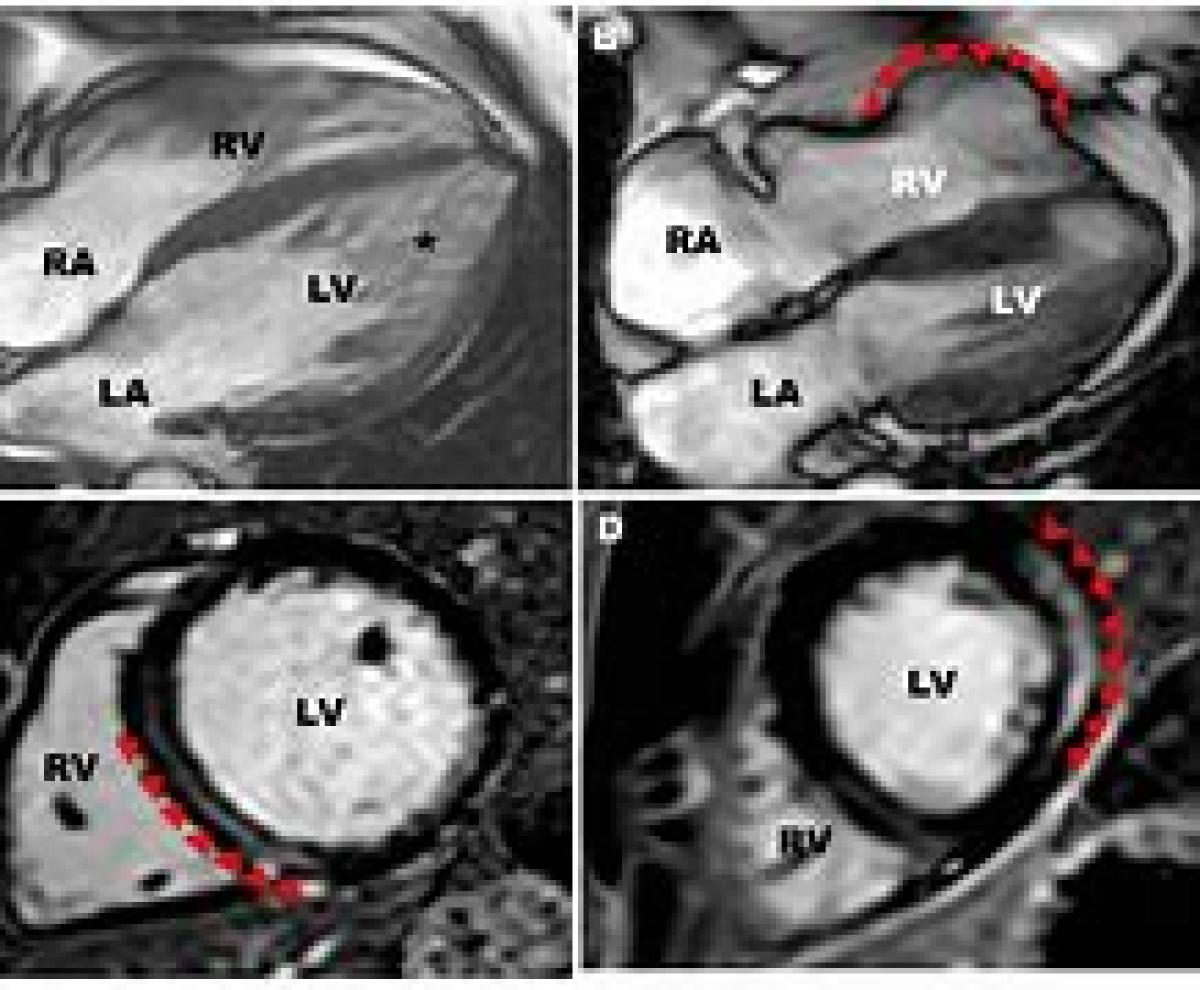

تصویربرداری تشدید مغناطیسی قلبی عروقی (CMR، همچنین به عنوان MRI قلبی نیز شناخته می‌شود) یک روش تصویربرداری غیر تهاجمی از عملکرد و ساختار سیستم قلبی عروقی است. توالی MRI برای تصویربرداری قلب با استفاده از ECG (نوار قلب) و پروتکل‌های با وضوح زمانی بالا سازگار شده‌است. توسعه CMR یک زمینه فعال تحقیقاتی است و همچنان شاهد گسترش سریع تکنیک‌های جدید و نوظهور هستیم.

MRI قلبی و عروقی مکمل سایر روش‌های تصویر برداری، مانند سونو گرافی، سی تی اسکن قلبی و پزشکی هسته ای است. این روش نقش مهمی در مسیرهای تشخیصی و درمانی مبتنی بر شواهد در بیماری‌های قلبی عروقی دارد. کاربردهای CMR شامل ارزیابی بیماری شریان کرونری، بیماری‌های ماهیچه ای قلب، التهاب عضلات قلب، سرریز و زیادی آهن در خون، بیماری‌های عروقی و بیماری‌های مادرزادی قلب است. این یک استاندارد مرجع، جهت ارزیابی ساختار و عملکرد قلب است، و برای تشخیص و جراحی در بیماری‌های پیچیده مادرزادی قلب، بسیار ارزشمند است.